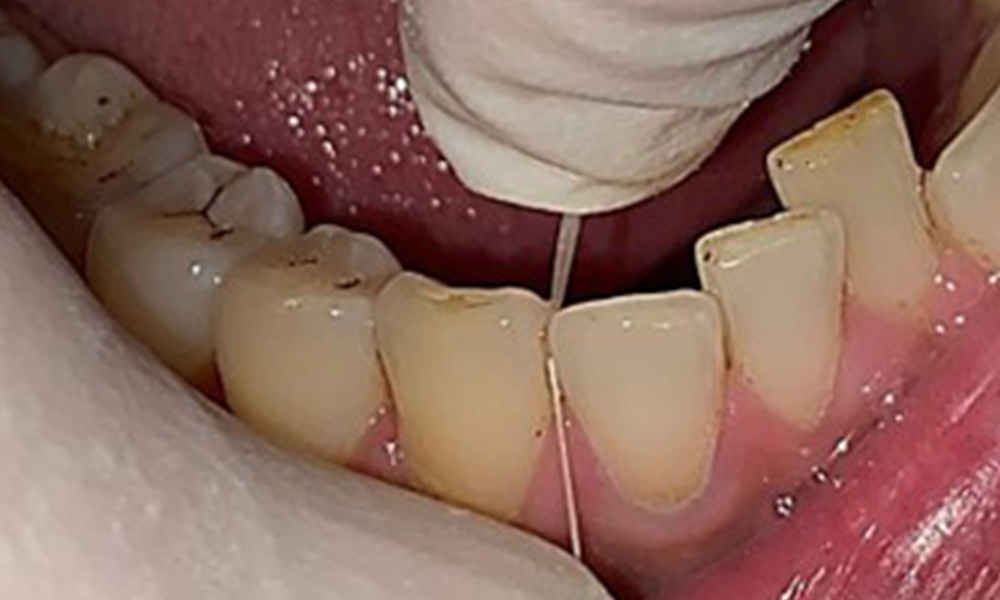

Il n'y a pas eu de résultats pathologiques extra-oraux. Lors de l'examen intrabuccal, l'inspection de la vue frontale a révélé une décoloration brunâtre près de la gencive kératinisée et à la transition vers la muqueuse mobile (Fig. 2), qui pourrait être attribuée à la consommation de nicotine. Des lésions blanchâtres de la muqueuse ont été observées sur le palais, en particulier près des surfaces palatines des molaires maxillaires, ce qui indique une kératinisation accrue et peut également être attribué à la consommation de nicotine. La langue était recouverte d'un enduit amovible blanc et brunâtre.

Le patient a une dentition complète avec un total de 28 dents. Il y avait des érosions et des attritions notables. (Fig. 4, Fig. 5). En raison du bruxisme, le patient a porté pendant de nombreuses années une attelle avec une gouttière ajustée la nuit. Les érosions ont été causées par une consommation prolongée de boissons isotoniques. Aucune perte d'os parodontal ou carie active n'a été observée.